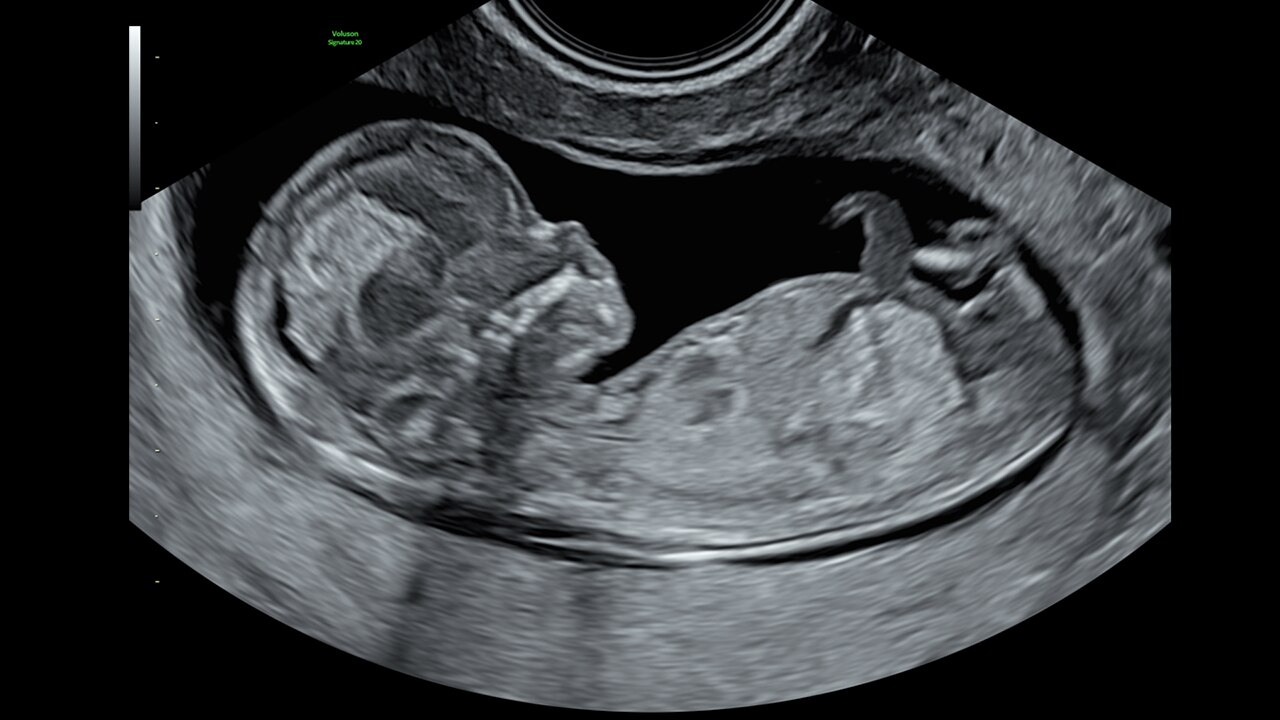

Next level color Doppler that delivers exceptional sensitivity for easy, fast visualization of blood flow, displaying a 3D like appearance as seen in this 27-week fetal heart.